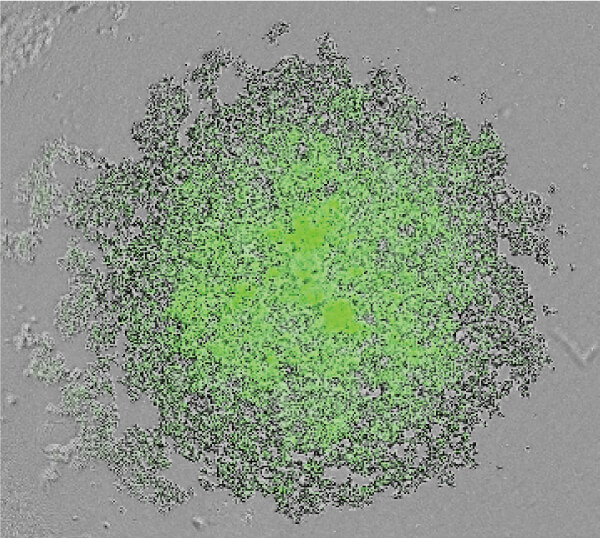

NoviSightを用いた病理マーカー解析

- 肺腺がん由来F-PDO®(RLUN14、RLUN20)と肺扁平上皮がん由来F-PDO®(RLUN16、RLUN21)を、肺腺がんマーカーのTIF1、肺扁平上皮がんマーカーのp63に対する抗体を用いて、免疫染色を行った。

- 病理診断と同様に、肺腺がん由来F-PDO®はTIF1抗体で、肺扁平上皮がん由来F-PDO®はp63抗体で染色された。

- それぞれのF-PDO®の細胞塊あたりの陽性細胞率をNoviSightを用いて算出した。その結果、有意差をもって、それぞれのマーカーに対して高い陽性率を示した。

| TTF1(肺腺がんマーカー) | |||

|---|---|---|---|

| 腺がん RLUN14 | 扁平上皮がん RLUN16 | コロイド腺がん RLUN20 | 扁平上皮がん RLUN21 |

これらのデータはオリンパス株式会社との共同研究により取得しました